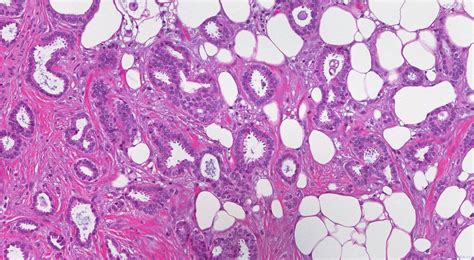

So, what exactly is invasive ductal carcinoma, or IDC? Let’s get down to brass tacks. Invasive ductal carcinoma of the right breast is the most common type of breast cancer. It originates in the milk ducts, which are the tiny tubes that carry milk to the nipple. When the cancer cells break through the wall of the duct and invade the surrounding breast tissue, it’s then classified as invasive . Think of it like a tiny seed sprouting and growing beyond its designated pot. This invasion means the cancer has the potential to spread, or metastasize, to other parts of the body, such as the lymph nodes or even more distant organs. It’s a serious diagnosis, no doubt, but understanding its nature is the first step in combating it. The key word here is invasive , as opposed to in situ , where the cancer cells are contained within the duct and haven’t spread. The ductal part tells us where it started, and the carcinoma simply means it’s a type of cancer that begins in epithelial cells, which line surfaces like the inside of ducts. When we talk about the right breast , it’s a specific localization that helps medical professionals pinpoint the exact location of the malignancy for treatment planning and record-keeping. This specificity is vital. In the realm of medical coding, precision is king, and that’s where the ICD-10 system comes in. It’s a standardized way for healthcare providers to classify and code all diagnoses, symptoms, and procedures. Each code tells a story, and for invasive ductal carcinoma of the right breast, that story is one of a specific, prevalent form of cancer requiring targeted medical attention. We’ll explore the specific ICD-10 codes associated with this diagnosis later, but for now, it’s good to have a solid grasp of what we’re dealing with when we hear this term. The implications of this diagnosis extend far beyond the patient, impacting healthcare systems, research efforts, and public health initiatives. Therefore, accurate coding is not just an administrative task; it’s a fundamental component of effective healthcare delivery.